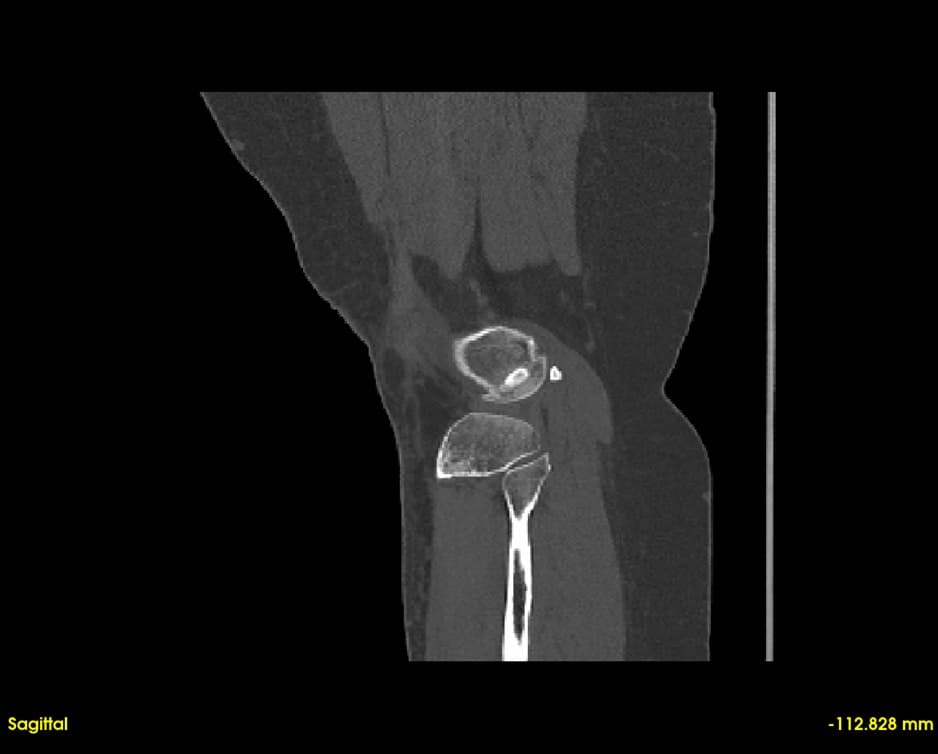

Simultaneous axial, sagittal, and coronal views. Navigate through slices with synchronized cross-referencing.

Explore slices with multi-planar reconstruction views

Quickly visualize and analyze anatomical structures from CT and MRI scans. Identify abnormalities with precise 3D visualization.